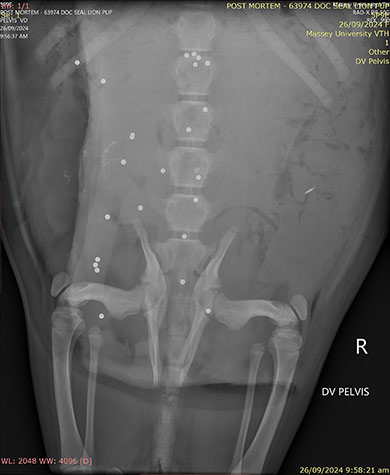

X-ray of the sea lion showing shotgun pellets

Image: Massey University